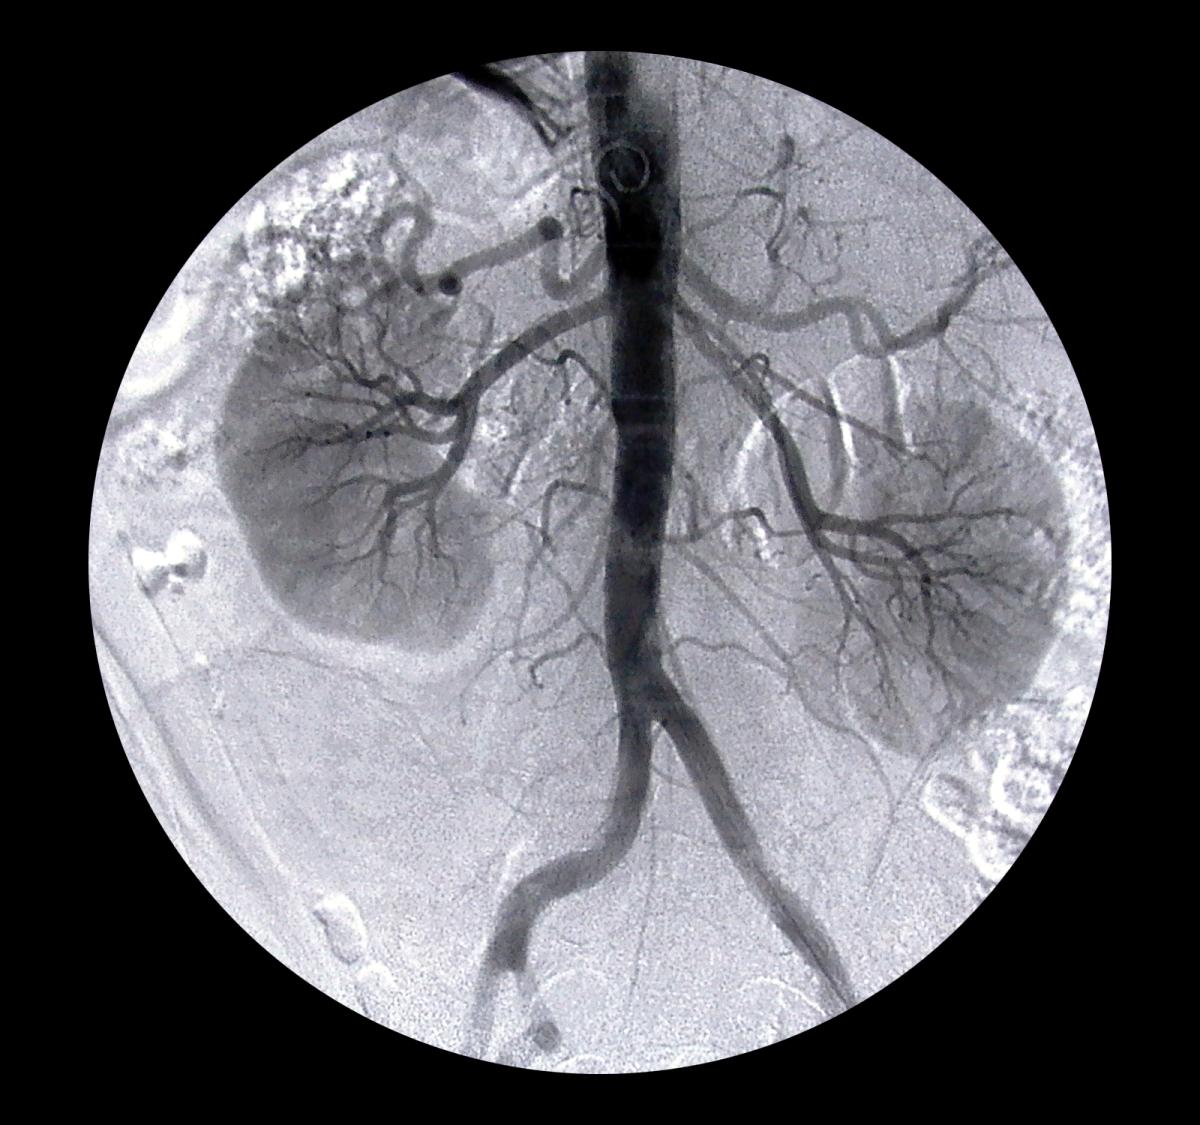

Buenas tardes: no se me ordenó un cateterismo por tener 1.55 de creatinina consideran Ustedes que este valor es alto y de serlo que puedo hacer para bajarlo a lo normal, mil y mil gracias por su información . Wiliiam